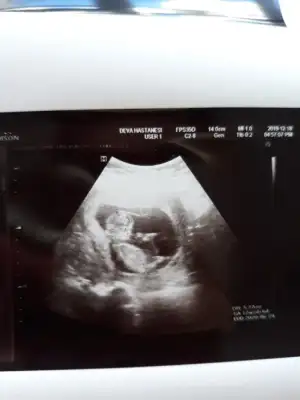

• 20191218_102242.webp

20191218_102242.webp

29,1 KB · Görüntüleme: 53

Ikra meyra Ikra meyra 12+0 ultrasonu:)

363C7916-792F-4CE1-9F27-A686FE4C5637.jpeg

Doktor %80 erkek dedi sizce net midir? Cok arkdsm